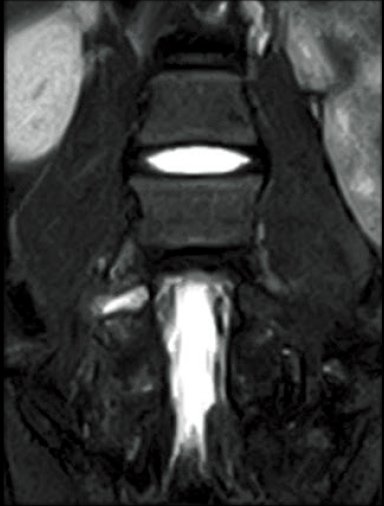

FatSep-T2WI

T2WI